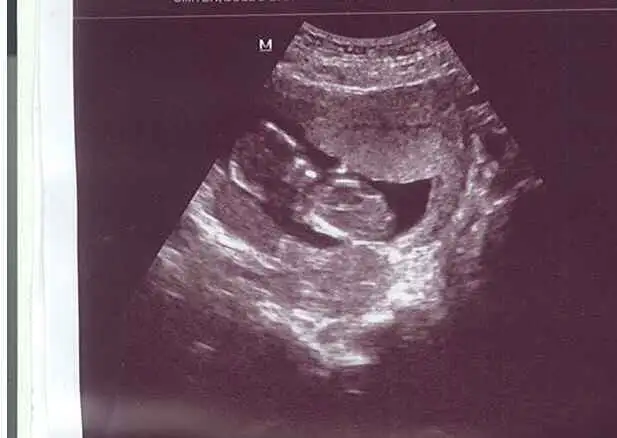

gurbet güzeli cnm bunlar en son fotolar 14+4 haftalık görüntüler...dr.10 gün öncesi kesin olmamakla beraber kıza benziyo demişti, bu hafta erkek dedi.bi bakarmısınız arkadaşlar sizce de erkek mi yoksa tekrar değişebilir mi?kafam cok karıstı..Eki Görüntüle 808673 Eki Görüntüle 808667

kızlar anlayanlar lütfen cvp versin ....lütfennn